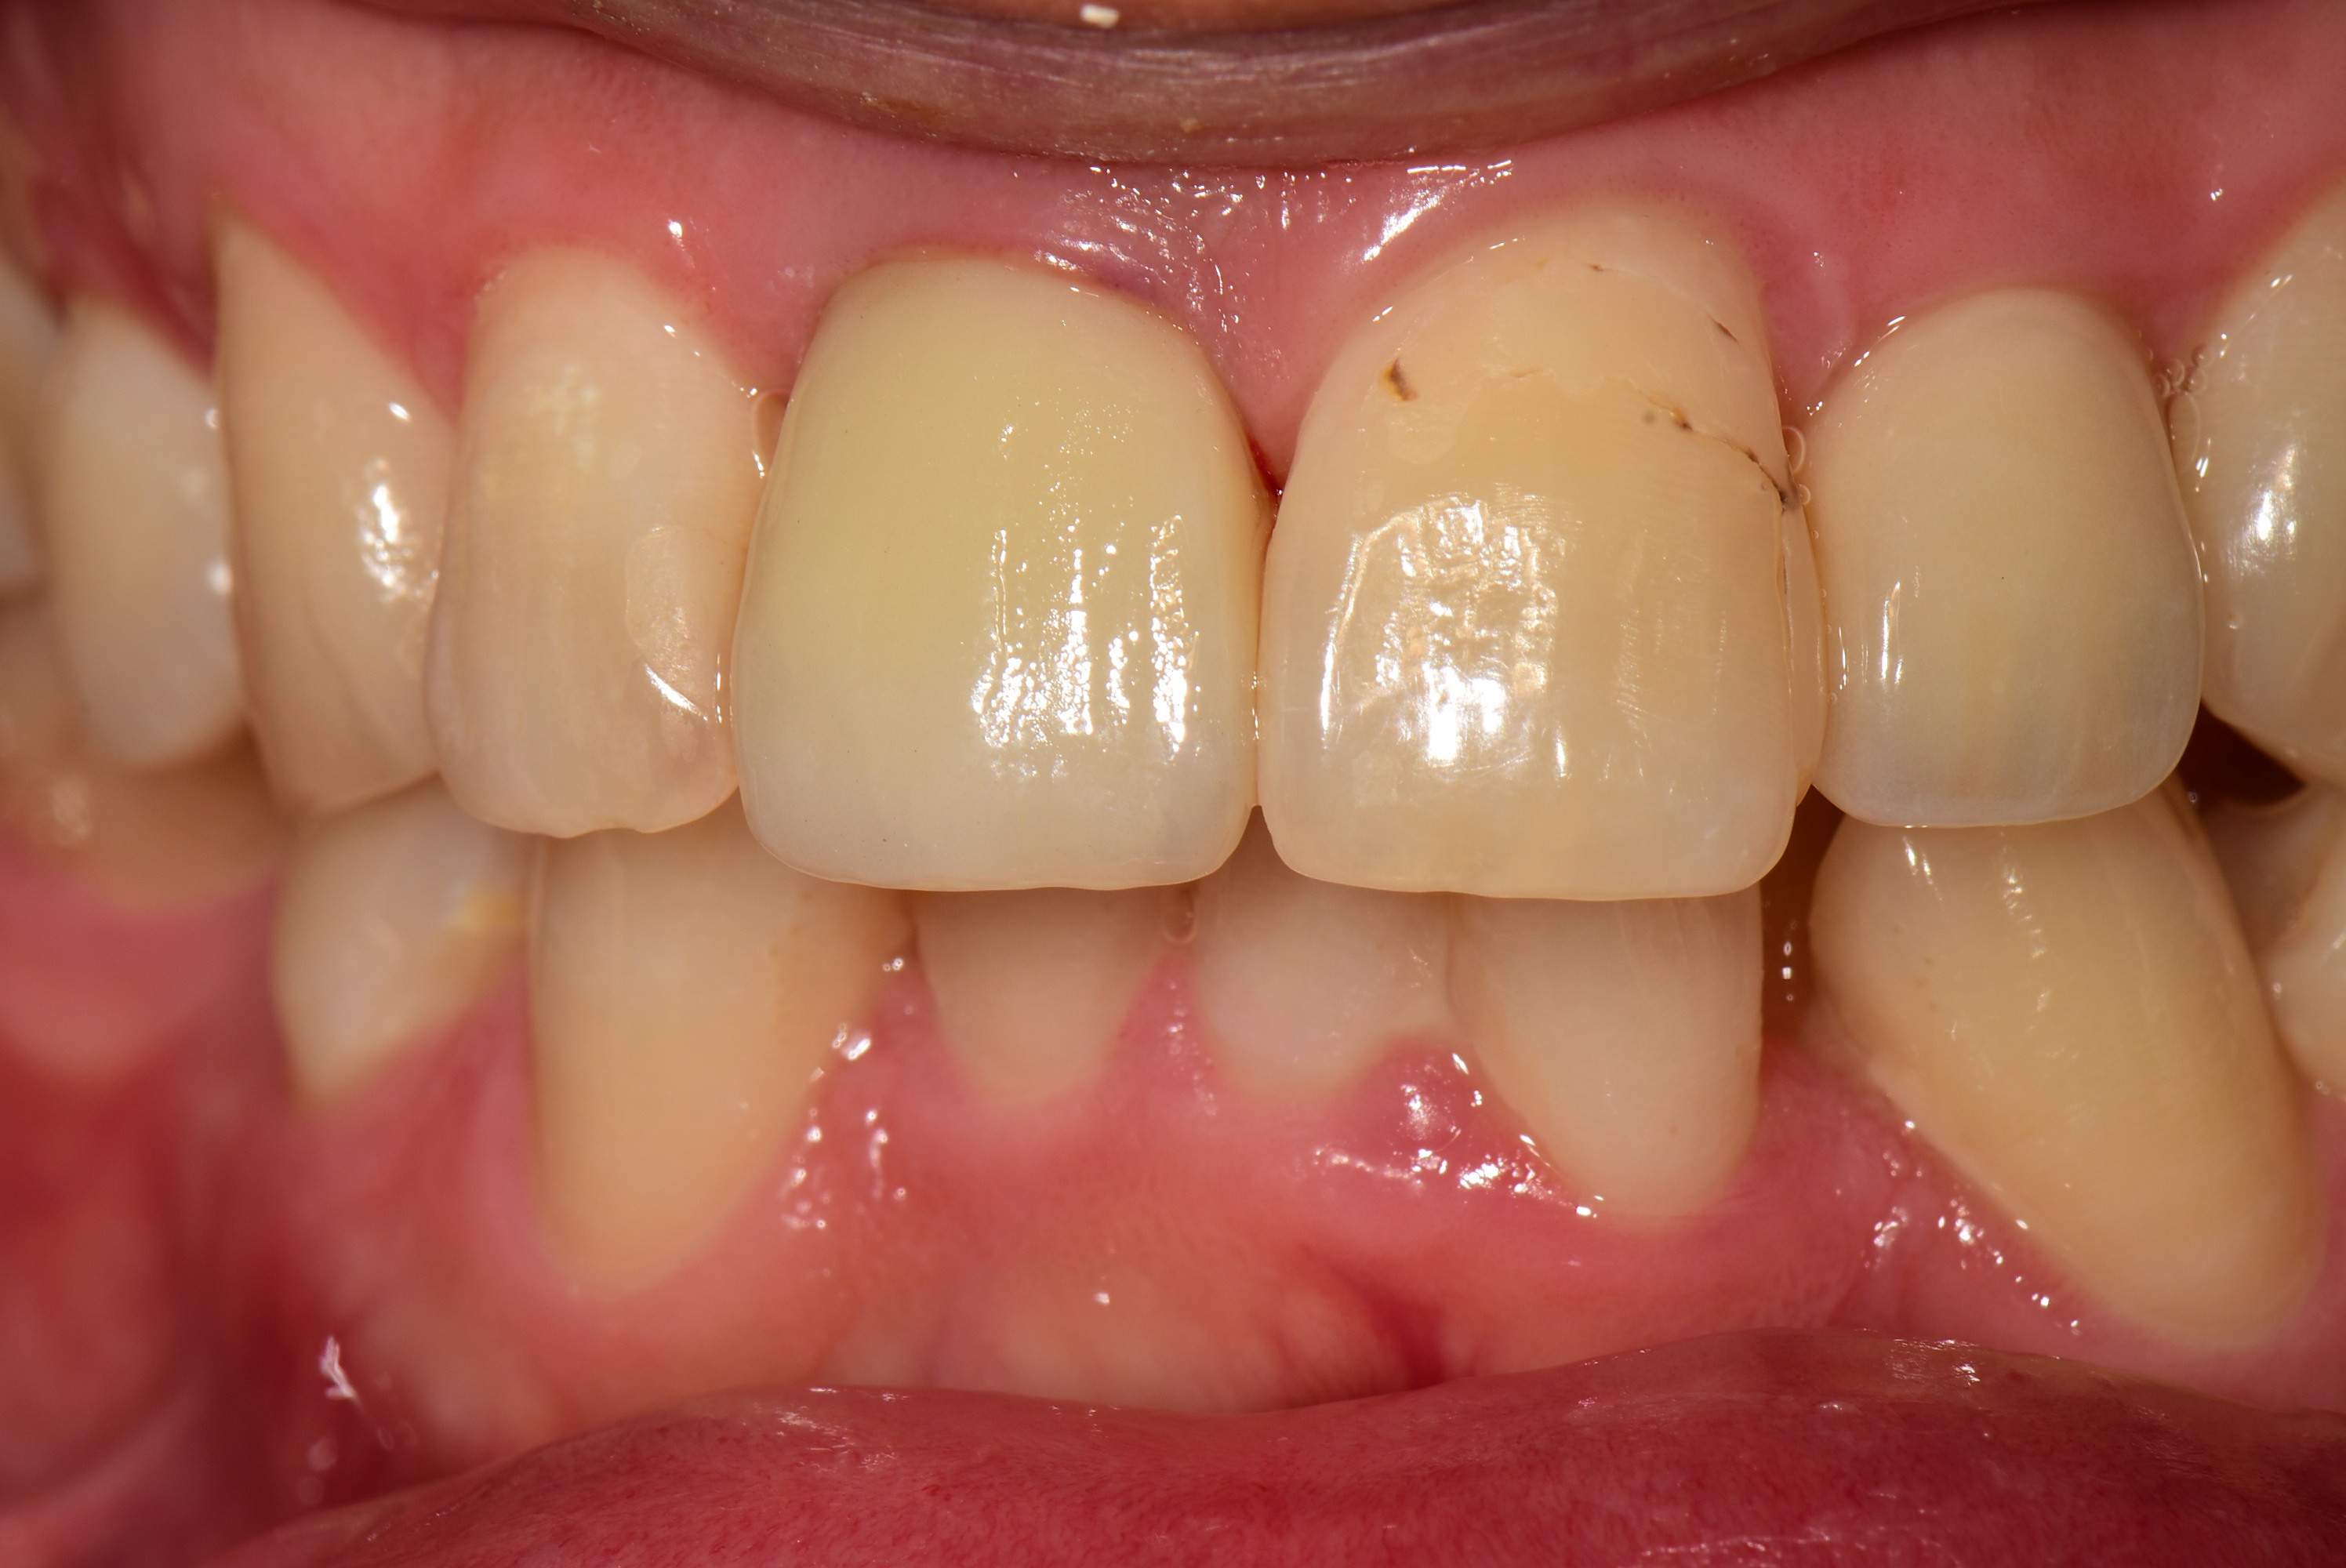

30대 남성분이 넘어져서 앞니가 흔들린다고 고촌치과에 내원하셨습니다.

CT 검사 결과 치아 머리 부분이 부러졌습니다.

살릴 수는 없는 상황이라 발치 즉시 임플란트와 즉시 임시치아를 계획하였습니다.

임플란트 식립후 임시치아를 바로 제작한 후 사진입니다.

아래는 3개월 후 최종 보철 후 사진입니다.